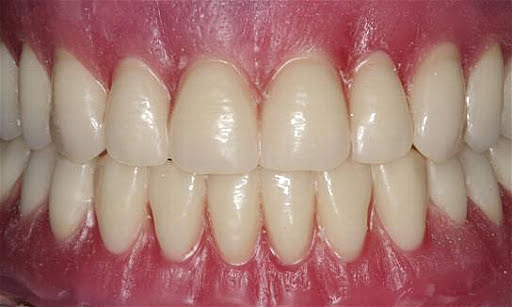

• Entrega prótesis removible.

Entrega prótesis removible.

Entrega y ajuste de prótesis removible.